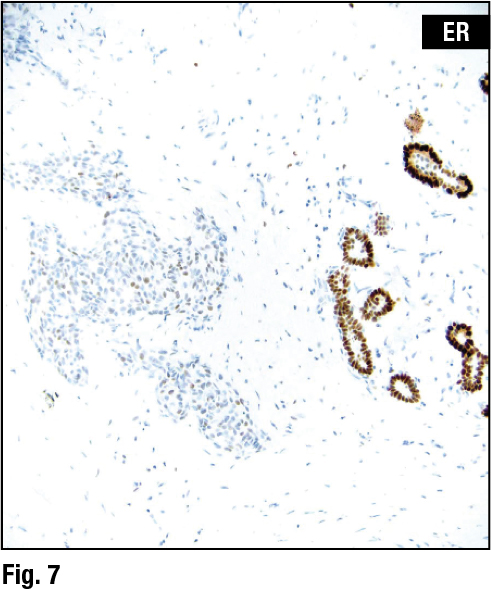

The first two case examples Dr. Collins presented dealt with the question: Is the malignancy in the breast a carcinoma? Case No. 1 is a core needle biopsy of a breast lesion sent to her group with the differential diagnosis of recurrent carcinoma versus fat necrosis. Presenting a split image of the lesion (Fig. 1), Dr. Collins pointed to (on left) “sheets of tumor cells infiltrating the stroma and into the fat.” On intermediate power in the image on the right, “you can see the very large pleomorphic cells with very high-grade nuclei,” she said. She also pointed out a zone of necrosis in the lower part of the right image and said there were other areas of necrosis. She described another image of the lesion as displaying “again very pleomorphic nuclei, brisk mitotic rate, and single cell necrosis.”

The pathologic diagnosis rendered was invasive ductal carcinoma, grade three. The tumor was found to be estrogen and progesterone receptor negative and HER2 negative, which Dr. Collins said might be expected with something that looks this bad. When the case was presented at the weekly radiology-pathology correlation conference, however, the radiologists shared clinical information suggesting a different malignancy. “They told us that clinically these were violaceous plaques over large areas of the breast. It was almost oozing blood,” she said. “So this obviously raises the additional question of whether this might represent angiosarcoma.”

Additional testing revealed that the tumor was keratin negative and CD31 and factor VIII positive, resulting in a revised diagnosis of epithelioid angiosarcoma (Figs. 2 and 3). “One of the unfortunate consequences of radiation therapy is that you can get secondary angiosarcomas,” Dr. Collins tells CAP TODAY. “It’s very rare, but it has to be borne in mind.”